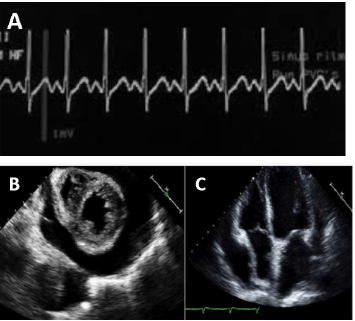

Homem de 64 anos, hipertenso e dislipidêmico, foi submetido à coronariografia eletiva via artéria radial direita, devido à angina progressiva aos esforços, refratária ao tratamento medicamentoso. Estava em uso de aspirina, atorvastatina, atenolol, anlodipina e mononitrato de isossorbida. O exame revelou duas lesões calcificadas de 80% no terço médio da artéria descendente anterior e 70% na região proximal da coronária direita. Foi submetido, no mesmo momento, à angioplastia com implante de 1 stent farmacológico em cada lesão. Duas horas após chegar na unidade cardiointensiva, o paciente evoluiu com rebaixamento do nível de consciência, palidez cutânea e PA: 78x40 mmHg.

O registro do ECG no monitor (A) e o ecocardiograma de urgência na beira do leito (B e C) estão dispostos a seguir.

Considerando o diagnóstico mais provável associado à piora clínica do caso anterior, assinale a opção que indica o que seria esperado encontrar no exame físico do paciente.